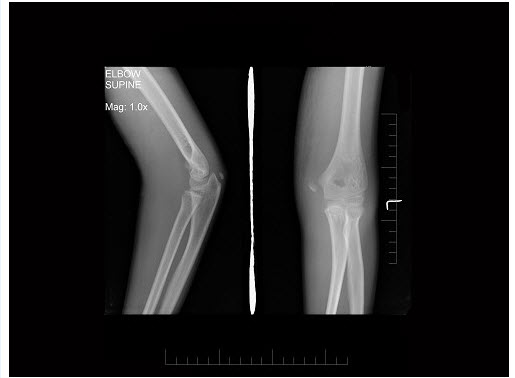

281、多项选择题 肘部继发性骨化中心包括()

A.肱骨小头骨化中心

B.滑车内侧部骨化中心

C.桡骨小头骨化中心

D.滑车外侧部骨化中心

E.内上髁和外上髁骨化中心